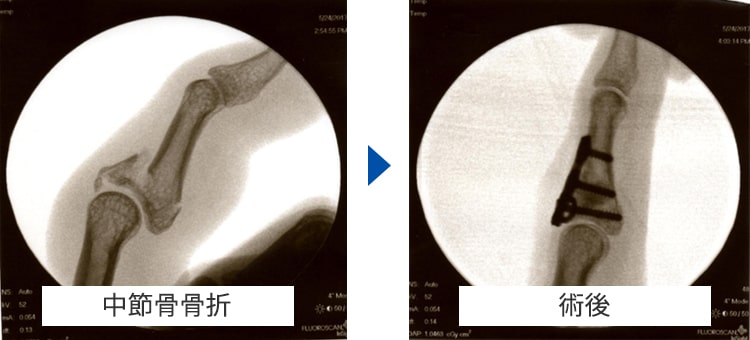

指骨・中手骨骨折

中手骨骨折 術前・術後写真

中手骨骨折術前・術後

原因

壁を殴ってしまったり、転倒した際に強打してしまったりして生じます。

症状

手や指が腫れて、痛くて動かせなくなります。変形を認める場合もあります。

治療方針

転位やズレの程度で治療方針を決めます。指の骨折の治療で重要なことは長期間固定をして拘縮を作らないことです。ほんの数週間の外固定により骨折部以外の関節も固くなってしまい、また少しの変形であっても指を握った時に重なったりする重篤な後遺症が生じることがありますので注意が必要です。手外科専門医にかかることをお勧めします。